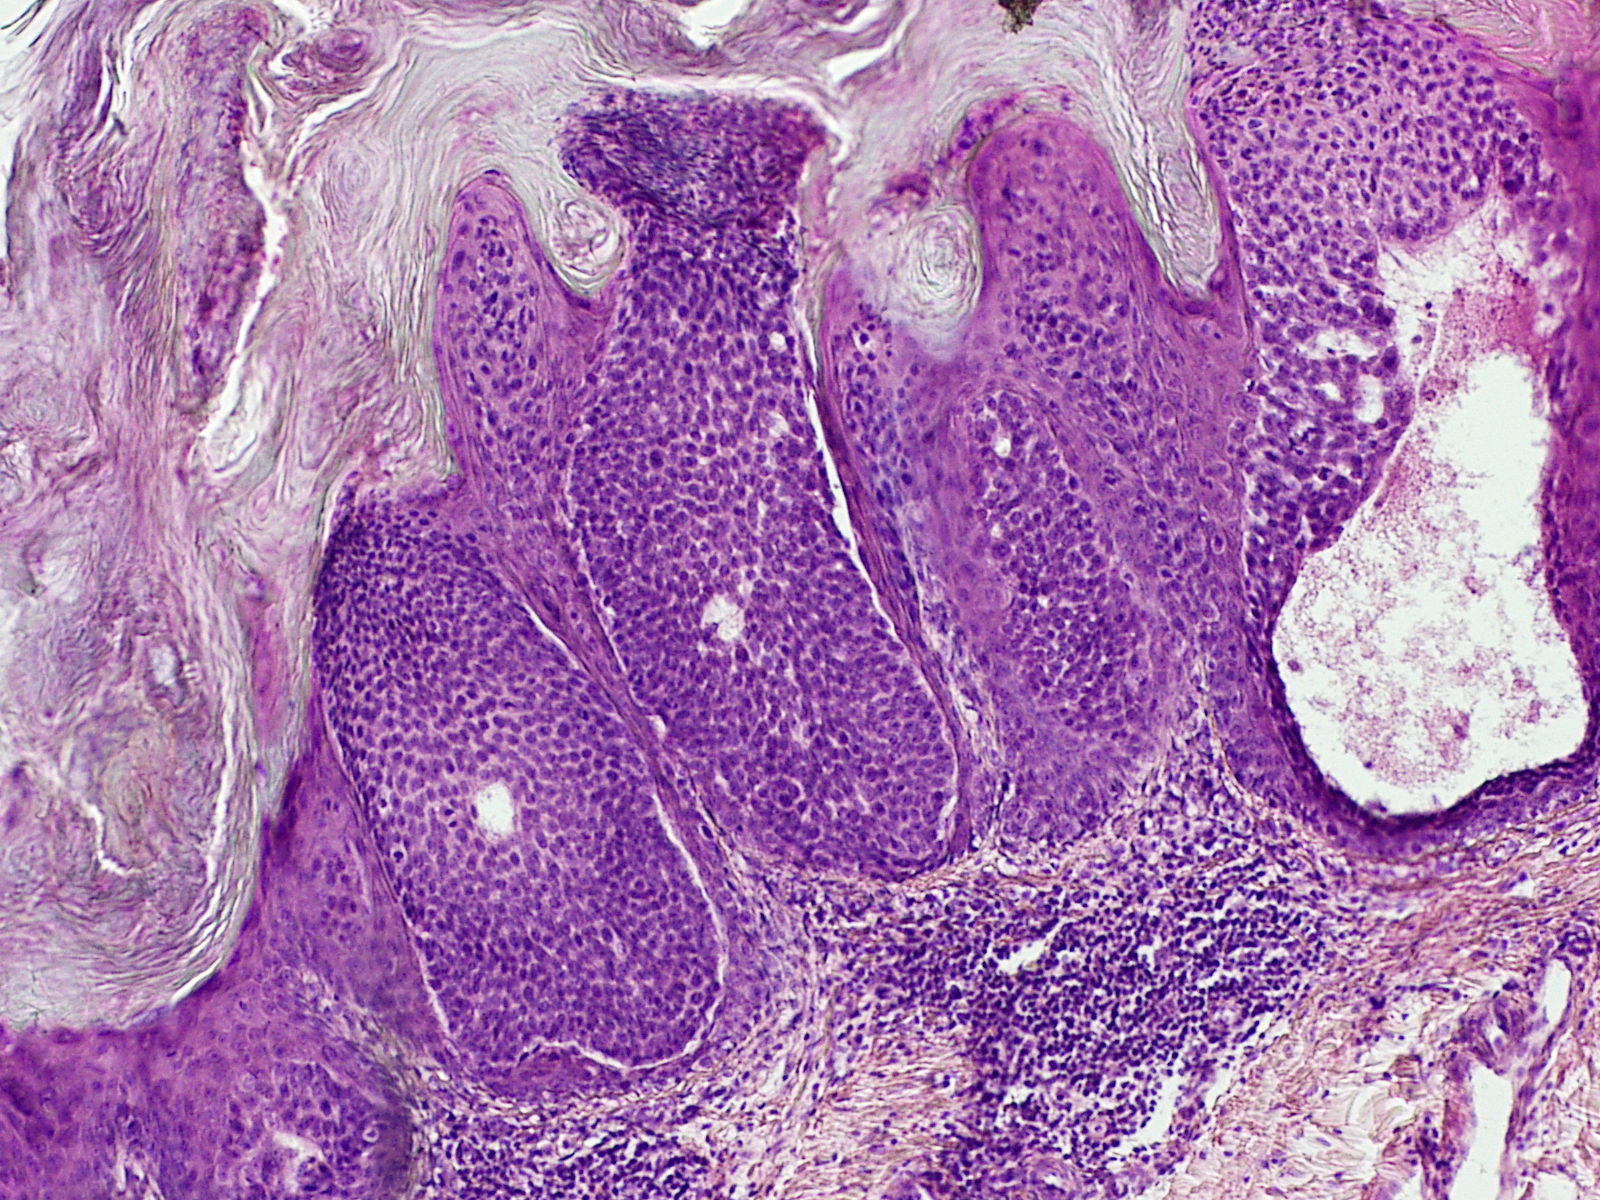

Hidroacanthoma simplex (synoniemen: intraepidermal

acrospiroma en intraepidermal eccrine poroma) is een benigne

adnextumortje opgebouwd uit dezelfde soort

acrosyringeale cellen die ook voorkomen in

eccrine poroma en

dermal duct tumor. Het hidroacanthoma

simplex kan dan ook beschouwd worden als een subtype eccrien poroma met een

bijzondere opbouw. Het is eerder een diagnose die op de PA zal worden gesteld

dan op de kliniek.

Hoge resolutie PA-foto rechts: Kevin Kwee en Afdeling Pathologie MUMC. Klik

op de afbeelding om in te zoomen.